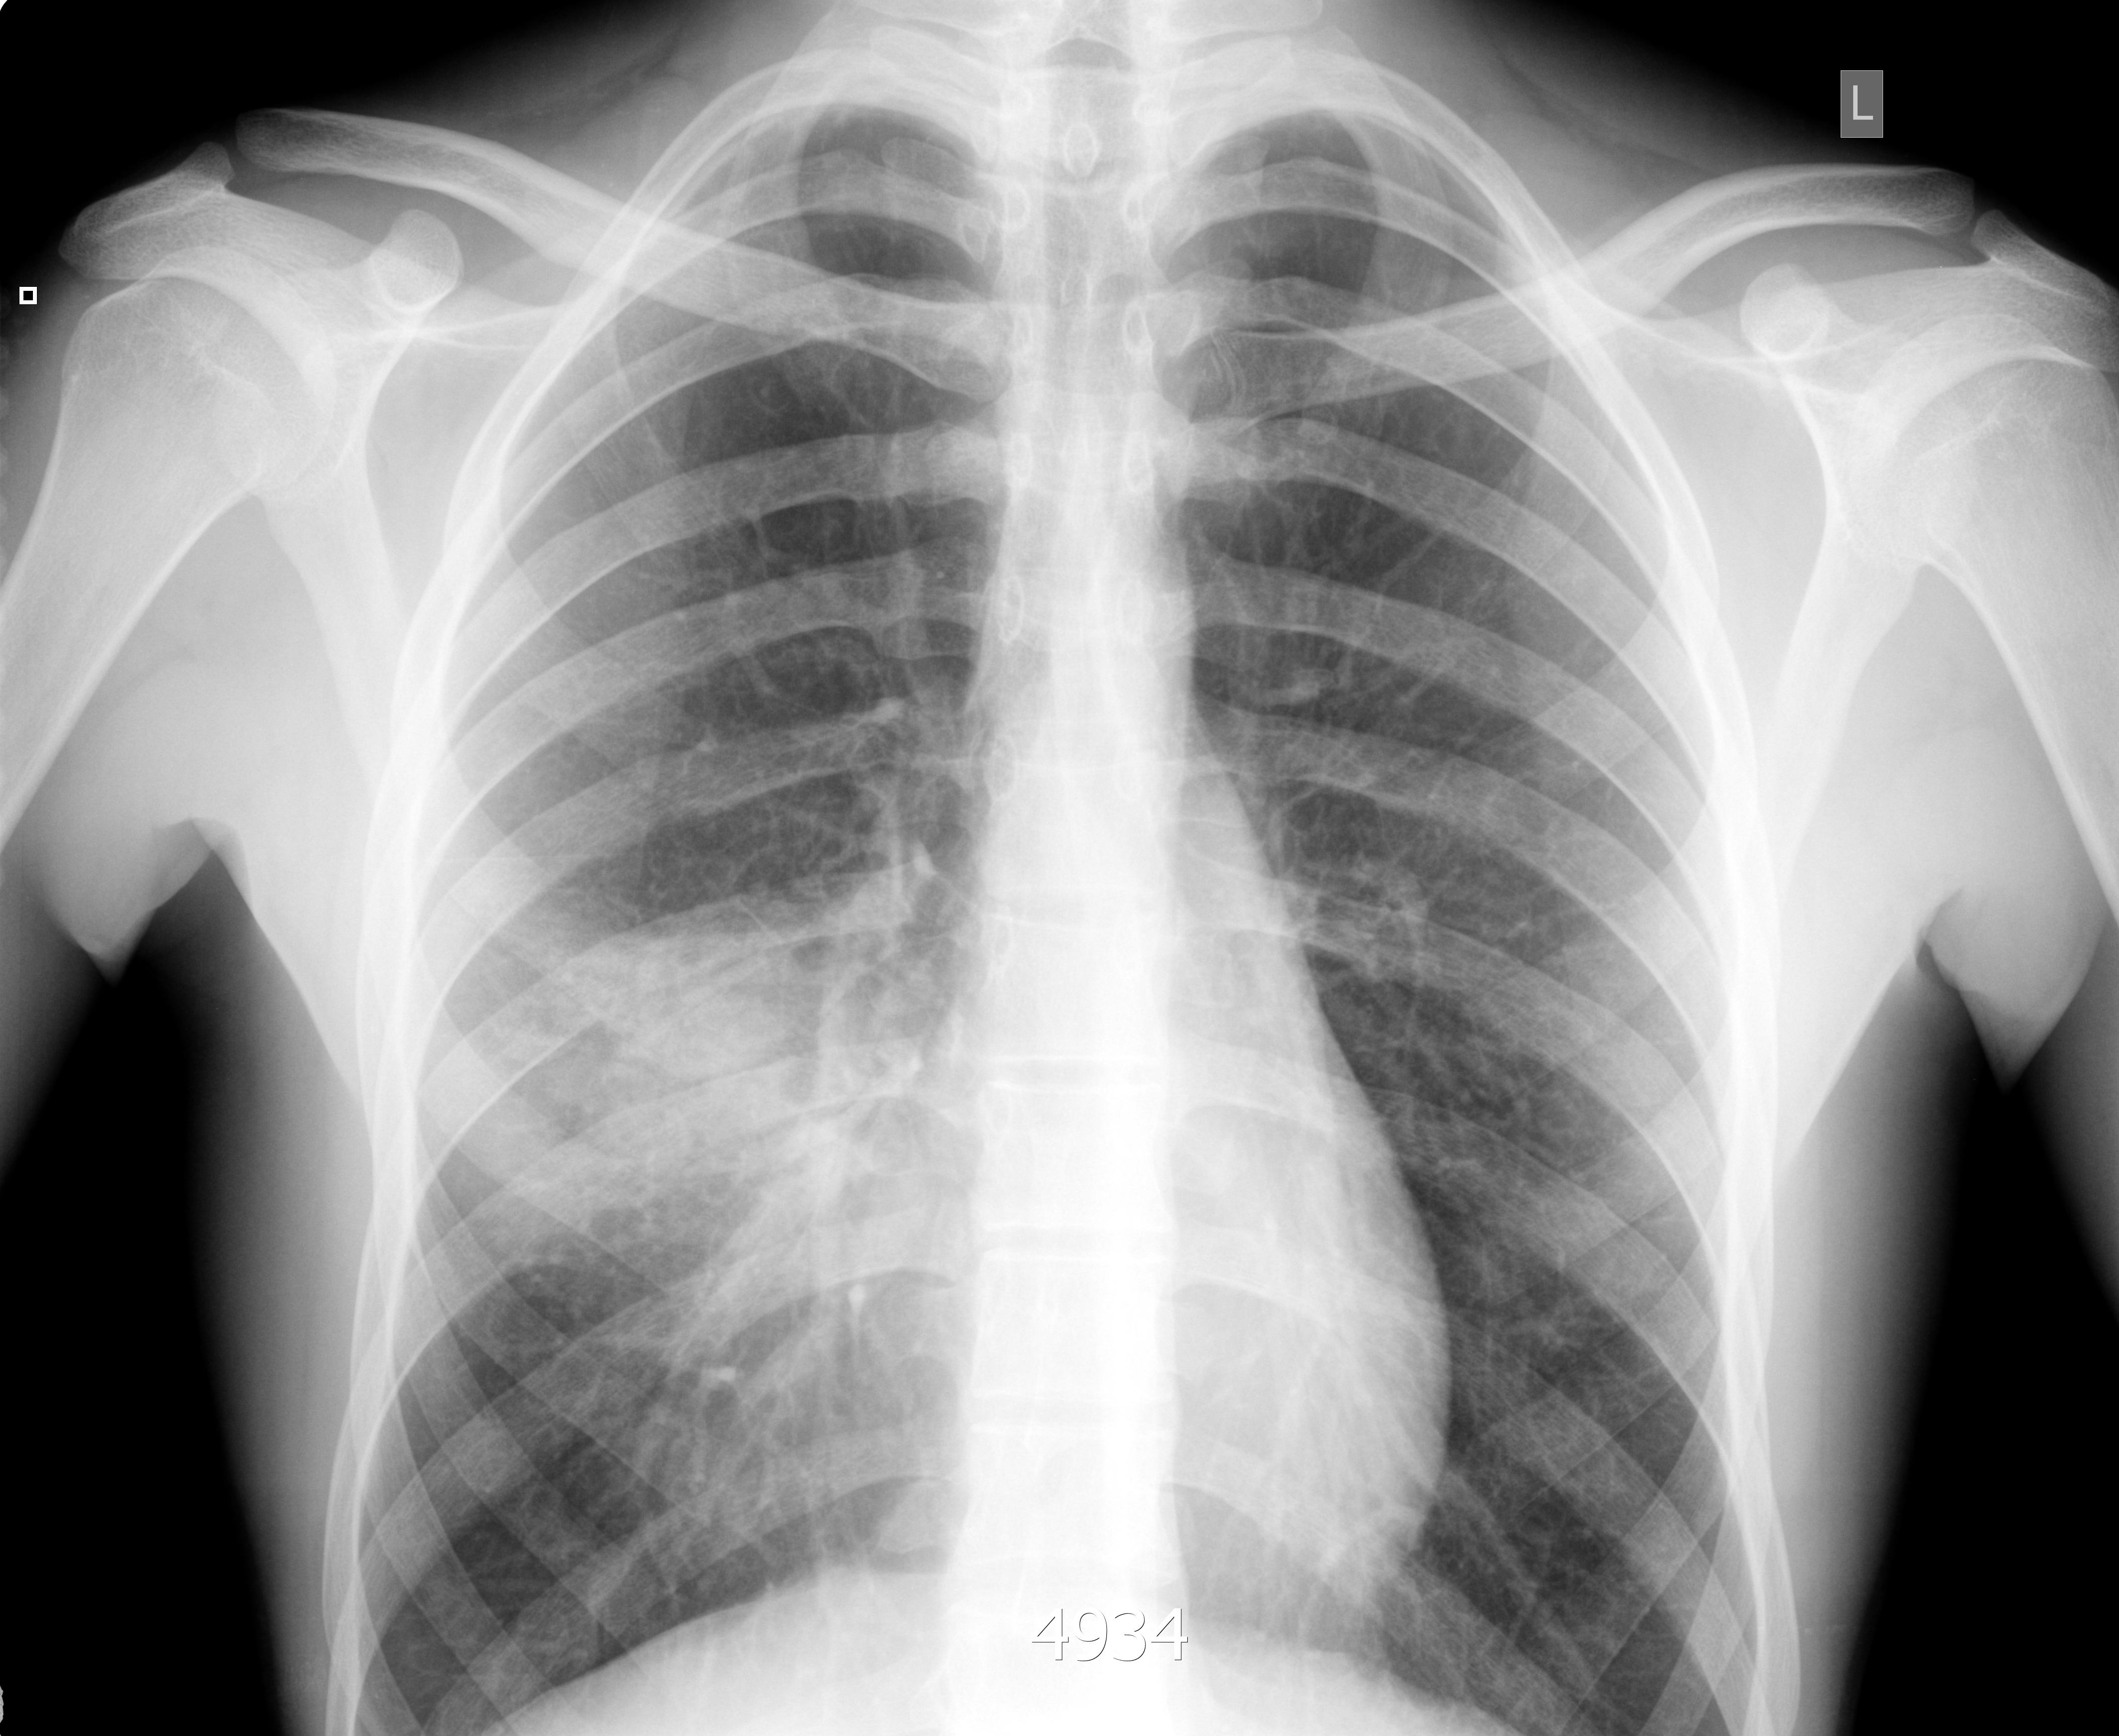

Правостороння пневмония, УЗИ и рентген

Молодой парень. Высокая температура, сухой кашель.